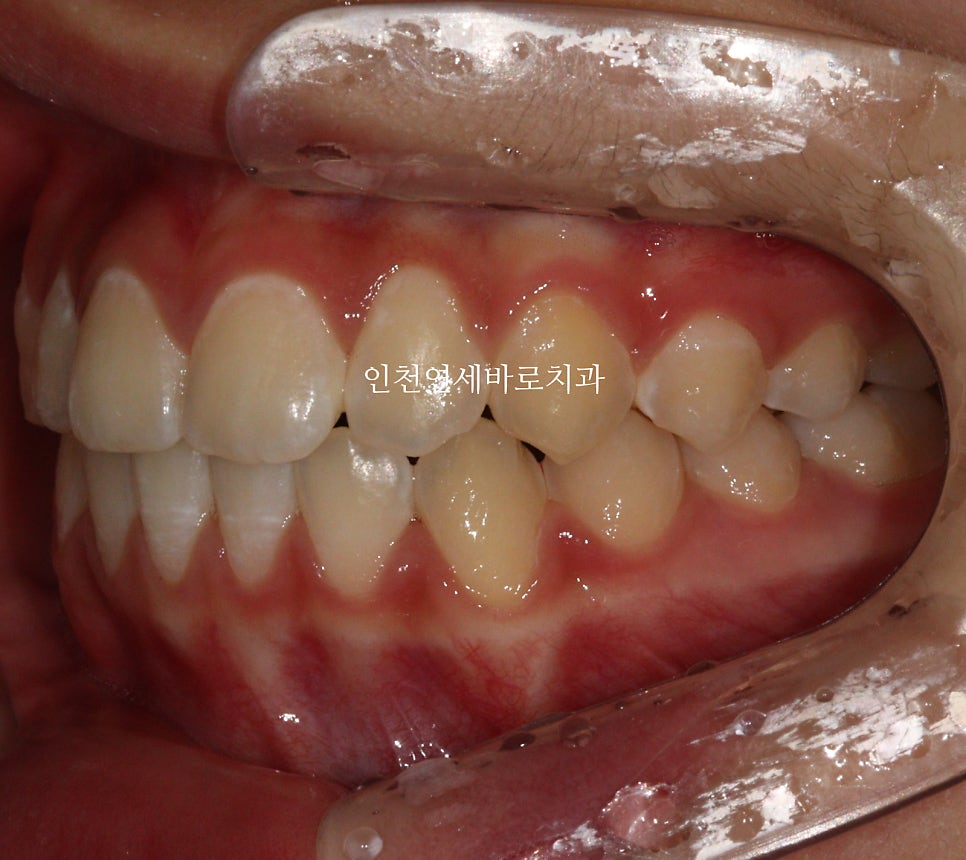

전 후 비교

인비절라인으로 치료하면 교합이 맞지 않는다. 라는 이상한 소문이 있습니다.

노하우와 경험, 실력이 있으면 문제없죠.

그래서 치료경험이 많은 곳을 잘 찾아 상담 받고 치료를 진행하시면 좋습니다

치아배열도 좋습니다.